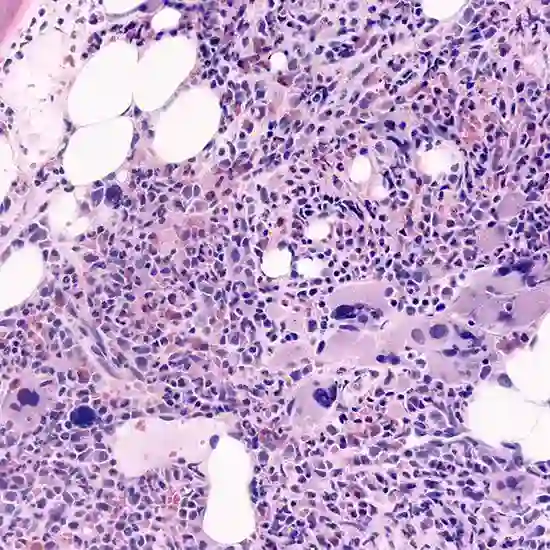

A physician may request a bone marrow biopsy, a method that pertains to taking and determining a specimen of bone marrow. If the tissue is healthy and the creation of blood cells is normal, healthcare practitioners can examine it.

An expert in medicine uses a small needle to take a sample of bone marrow into the needle during a bone marrow biopsy. In most cases, medical experts take a sample from the hip bone. Verified Source.

The sample is then examined for several malignancies and other disorders by a laboratory technician.

A pathologist, hematologist, or physician with expertise in blood will examine the samples.

Bone marrow biopsies are performed by medical specialists to examine illnesses and gauge blood cell production. Various biopsy results may point to a variety of illnesses.